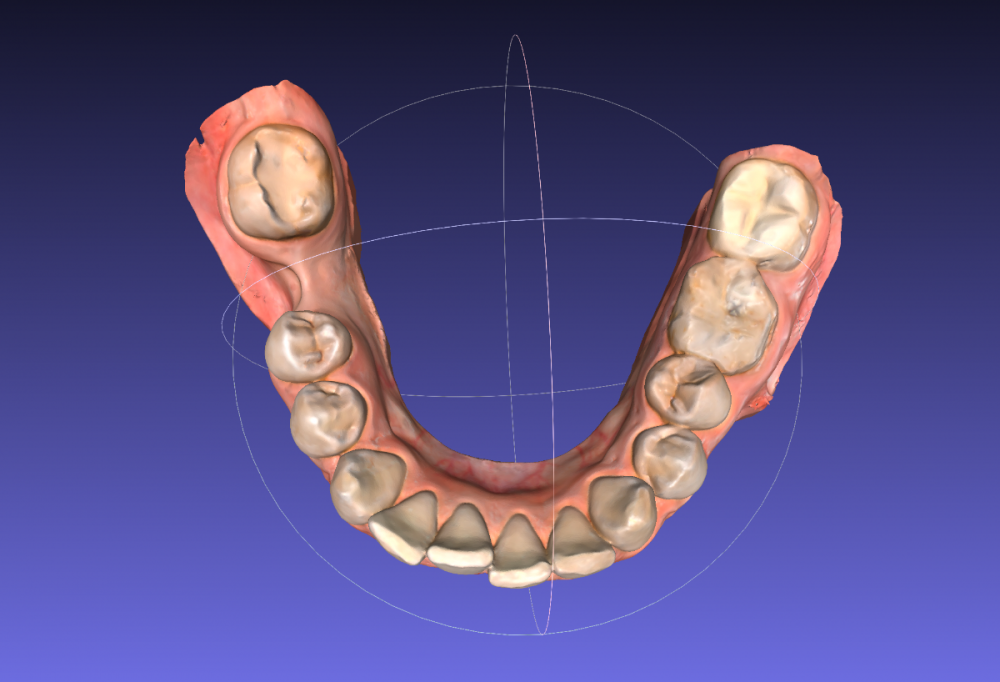

Сейчас я обратилась к ортодонтам с целью выровнять только нижний зубной ряд (искривлен из за воздействия 8ок), с последующей установкой импланта (46 зуб). Нижние восьмерки удалены.

26 отсутствует, 27 стоит на месте 26, 28 стоит на месте 27

Какие зубы имеют показания к удалению?

15-16 зуб - черная дыра - что это может быть? Есть ли шансы спасти?